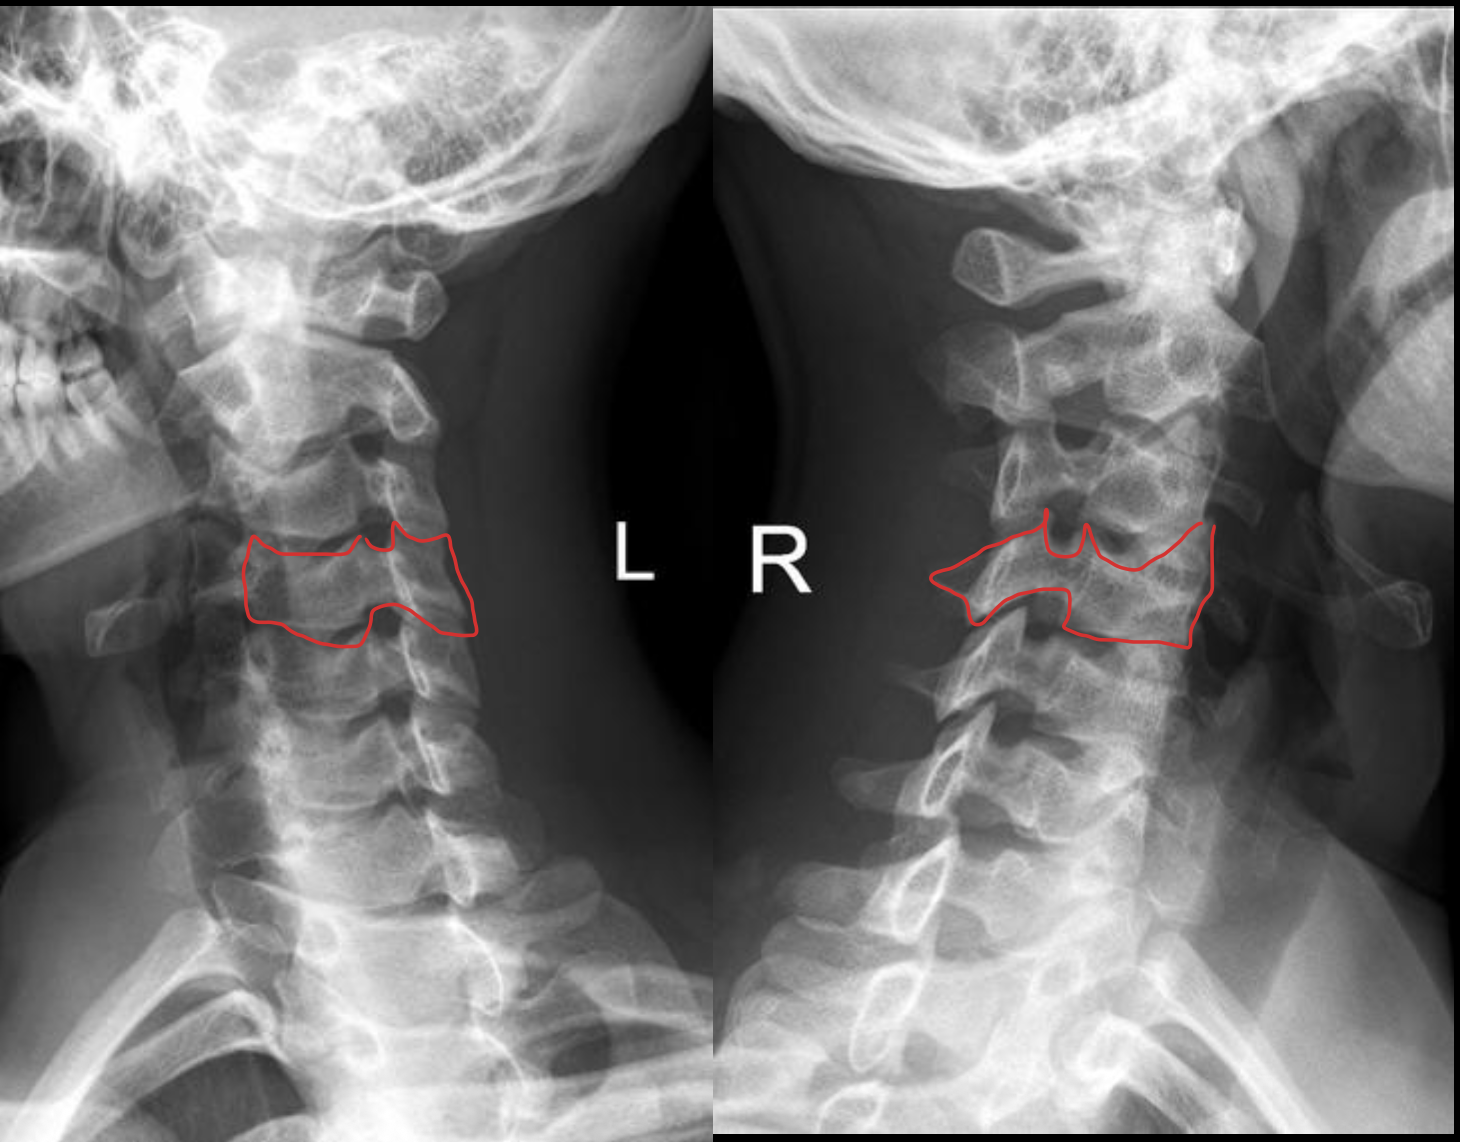

C4

c5